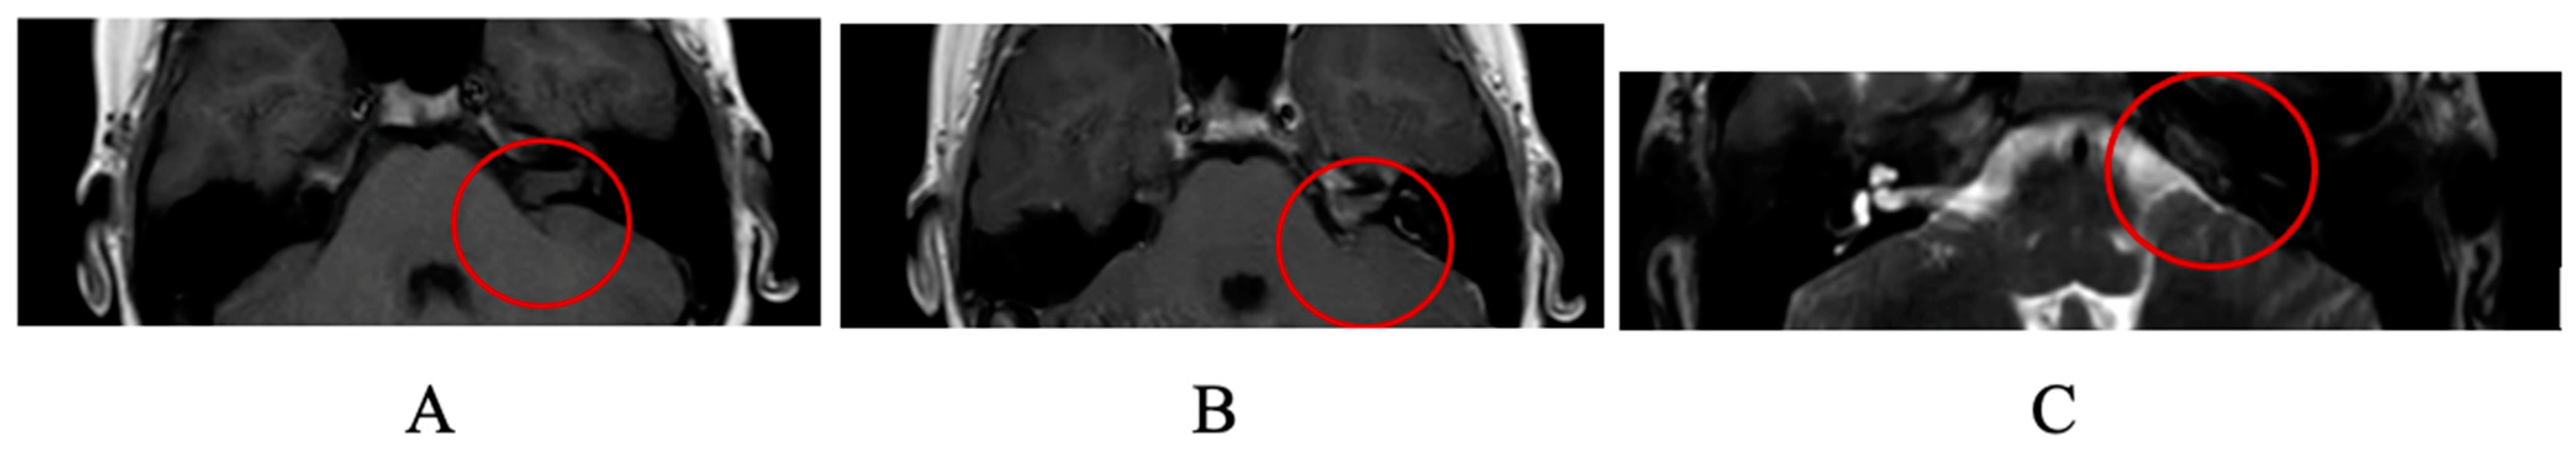

1. Case Report